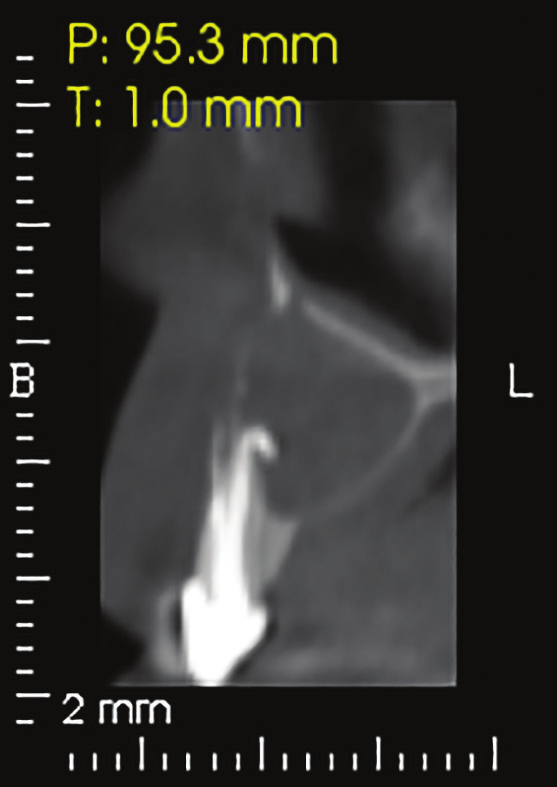

Figure 20: Periapical X-ray showing a 1.5 cm radiolucent lesion extending on apexes of teeth no 7 and 8 , note the lateral perforation on tooth no 7.

Figure 21: CAT view showing a radiolucent well circumscribed lesion with extended bone loss buccal, palatal and apical.

A 33 years-old male patient was visiting our clinic to replace missing teeth no 7 and 8. He was medically fit and mentioned that his teeth were lost due to car accident few years back. Intraoral examination shows absence of space for implant placement and restoration, orthodontic treatment was conducted for 18 sessions followed by surgical implant placement after stabilization of the occlusion. Following the restoration of the space, the amount of horizontal bone loss was evident both clinically and on CAT examinations (Fig.10, 11). A linear incision with mucoperiosteal flap elevation were conducted, the amount of horizontal bone loss was advanced (Fig. 12), which was an indication for autologous bone graft, patient refused to undergo an invasive surgery so PRF associated bovine bone was planned in the area. Blood withdrawal and centrifugation were done with preparation of both L-PRF membranes and sticky bone (bovine bone associated PRF) (Fig.13, 14,15). The combination was placed on the host bone deficiency and covered by a first layer of L-PRF membranes in order to stabilize the graft and insure hemostasis, the second layer of L-PRF membranes covered the cross linked collagen membrane placed in the same area and covering the first entity (Fig.16).